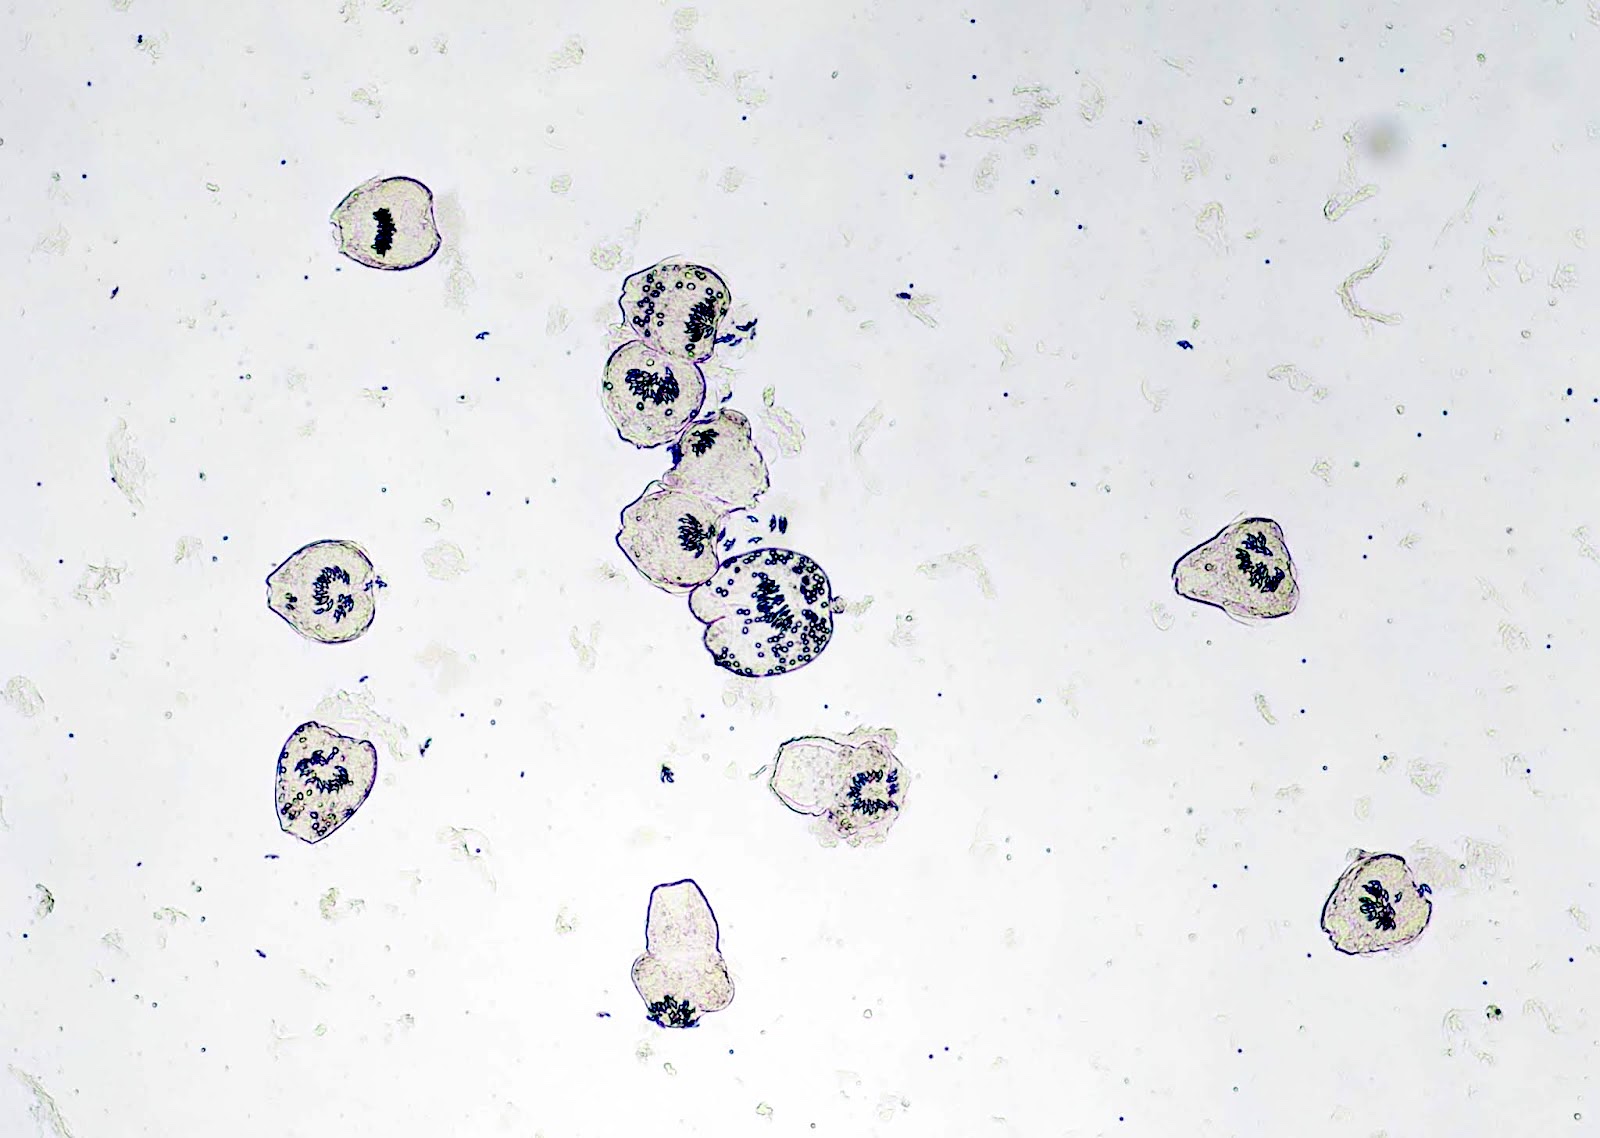

- Protoscolices, attached to the membrane and budding from it

- Protoscolices are ovoid and contain hooklets (birefringent under polarized light) and a sucker

Microscopic (histologic) images

Positive stains

- Hooklets are acid fast positive on Ziehl-Neelsen stain; also stain with GMS (J Cytol Histol 2016;7:1000422)